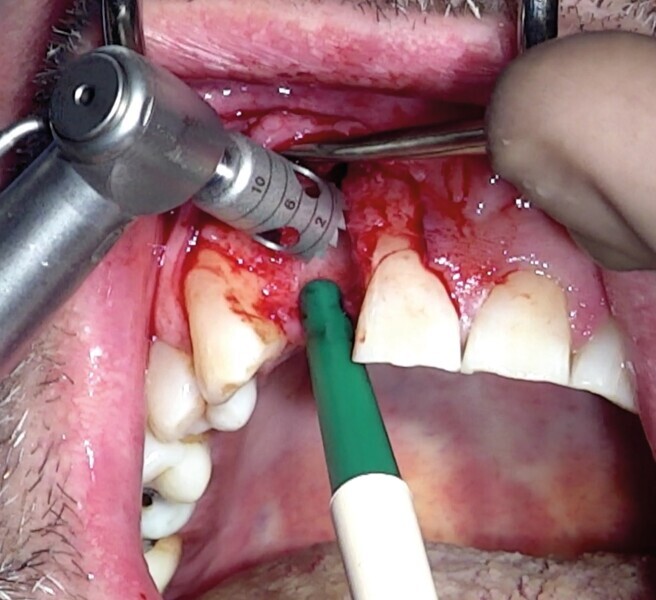

Dans certaines situations cliniques, l’étude radiologique tridimensionnelle montre un volume osseux exploitable en position de 18 ou 28. Il est alors aisé de réaliser le prélèvement au trépan, sur ces sites habituellement larges. Toute la pertinence dans ce cas est de le réaliser à travers la gencive kératinisée et obtenir ainsi une carotte ostéo-gingivale (Fig. 22). De ce fait, il ne faut pas faire d’incision ou de lambeau pour ouvrir l’accès au trépan. Le geste devient extrêmement rapide mais nécessite une bonne connaissance anatomique, une excellente analyse de la planification 3D, puis un bon repérage clinique.6

Pour connaître la profondeur de trépanation, il suffit d’enfoncer la sonde parodontale et de mesurer l’épaisseur de gencive sur l’os. En y ajoutant 4 mm, la profondeur finale est obtenue pour avoir suffisamment d’os. Une fois la carotte ostéogingivale prélevée (Figs. 23 et 24), il ne faut pas séparer l’os de la gencive, mais réduire l’épaisseur gingivale en supprimant la partie kératinisée (Fig. 25). Un implant cylindroconique (Straumann BLT 3,3 SLActive Roxolid) est parfaitement ancré (Fig. 26). La carotte d’os et sa gencive toujours adhérente, sont alors impactées transversalement à l’implant (Fig. 27). La partie osseuse spongieuse est au contact de l’implant, pendant que le conjonctif qui y est attaché, est utilisé comme un greffon conjonctif enfoui sous le lambeau vestibulaire.